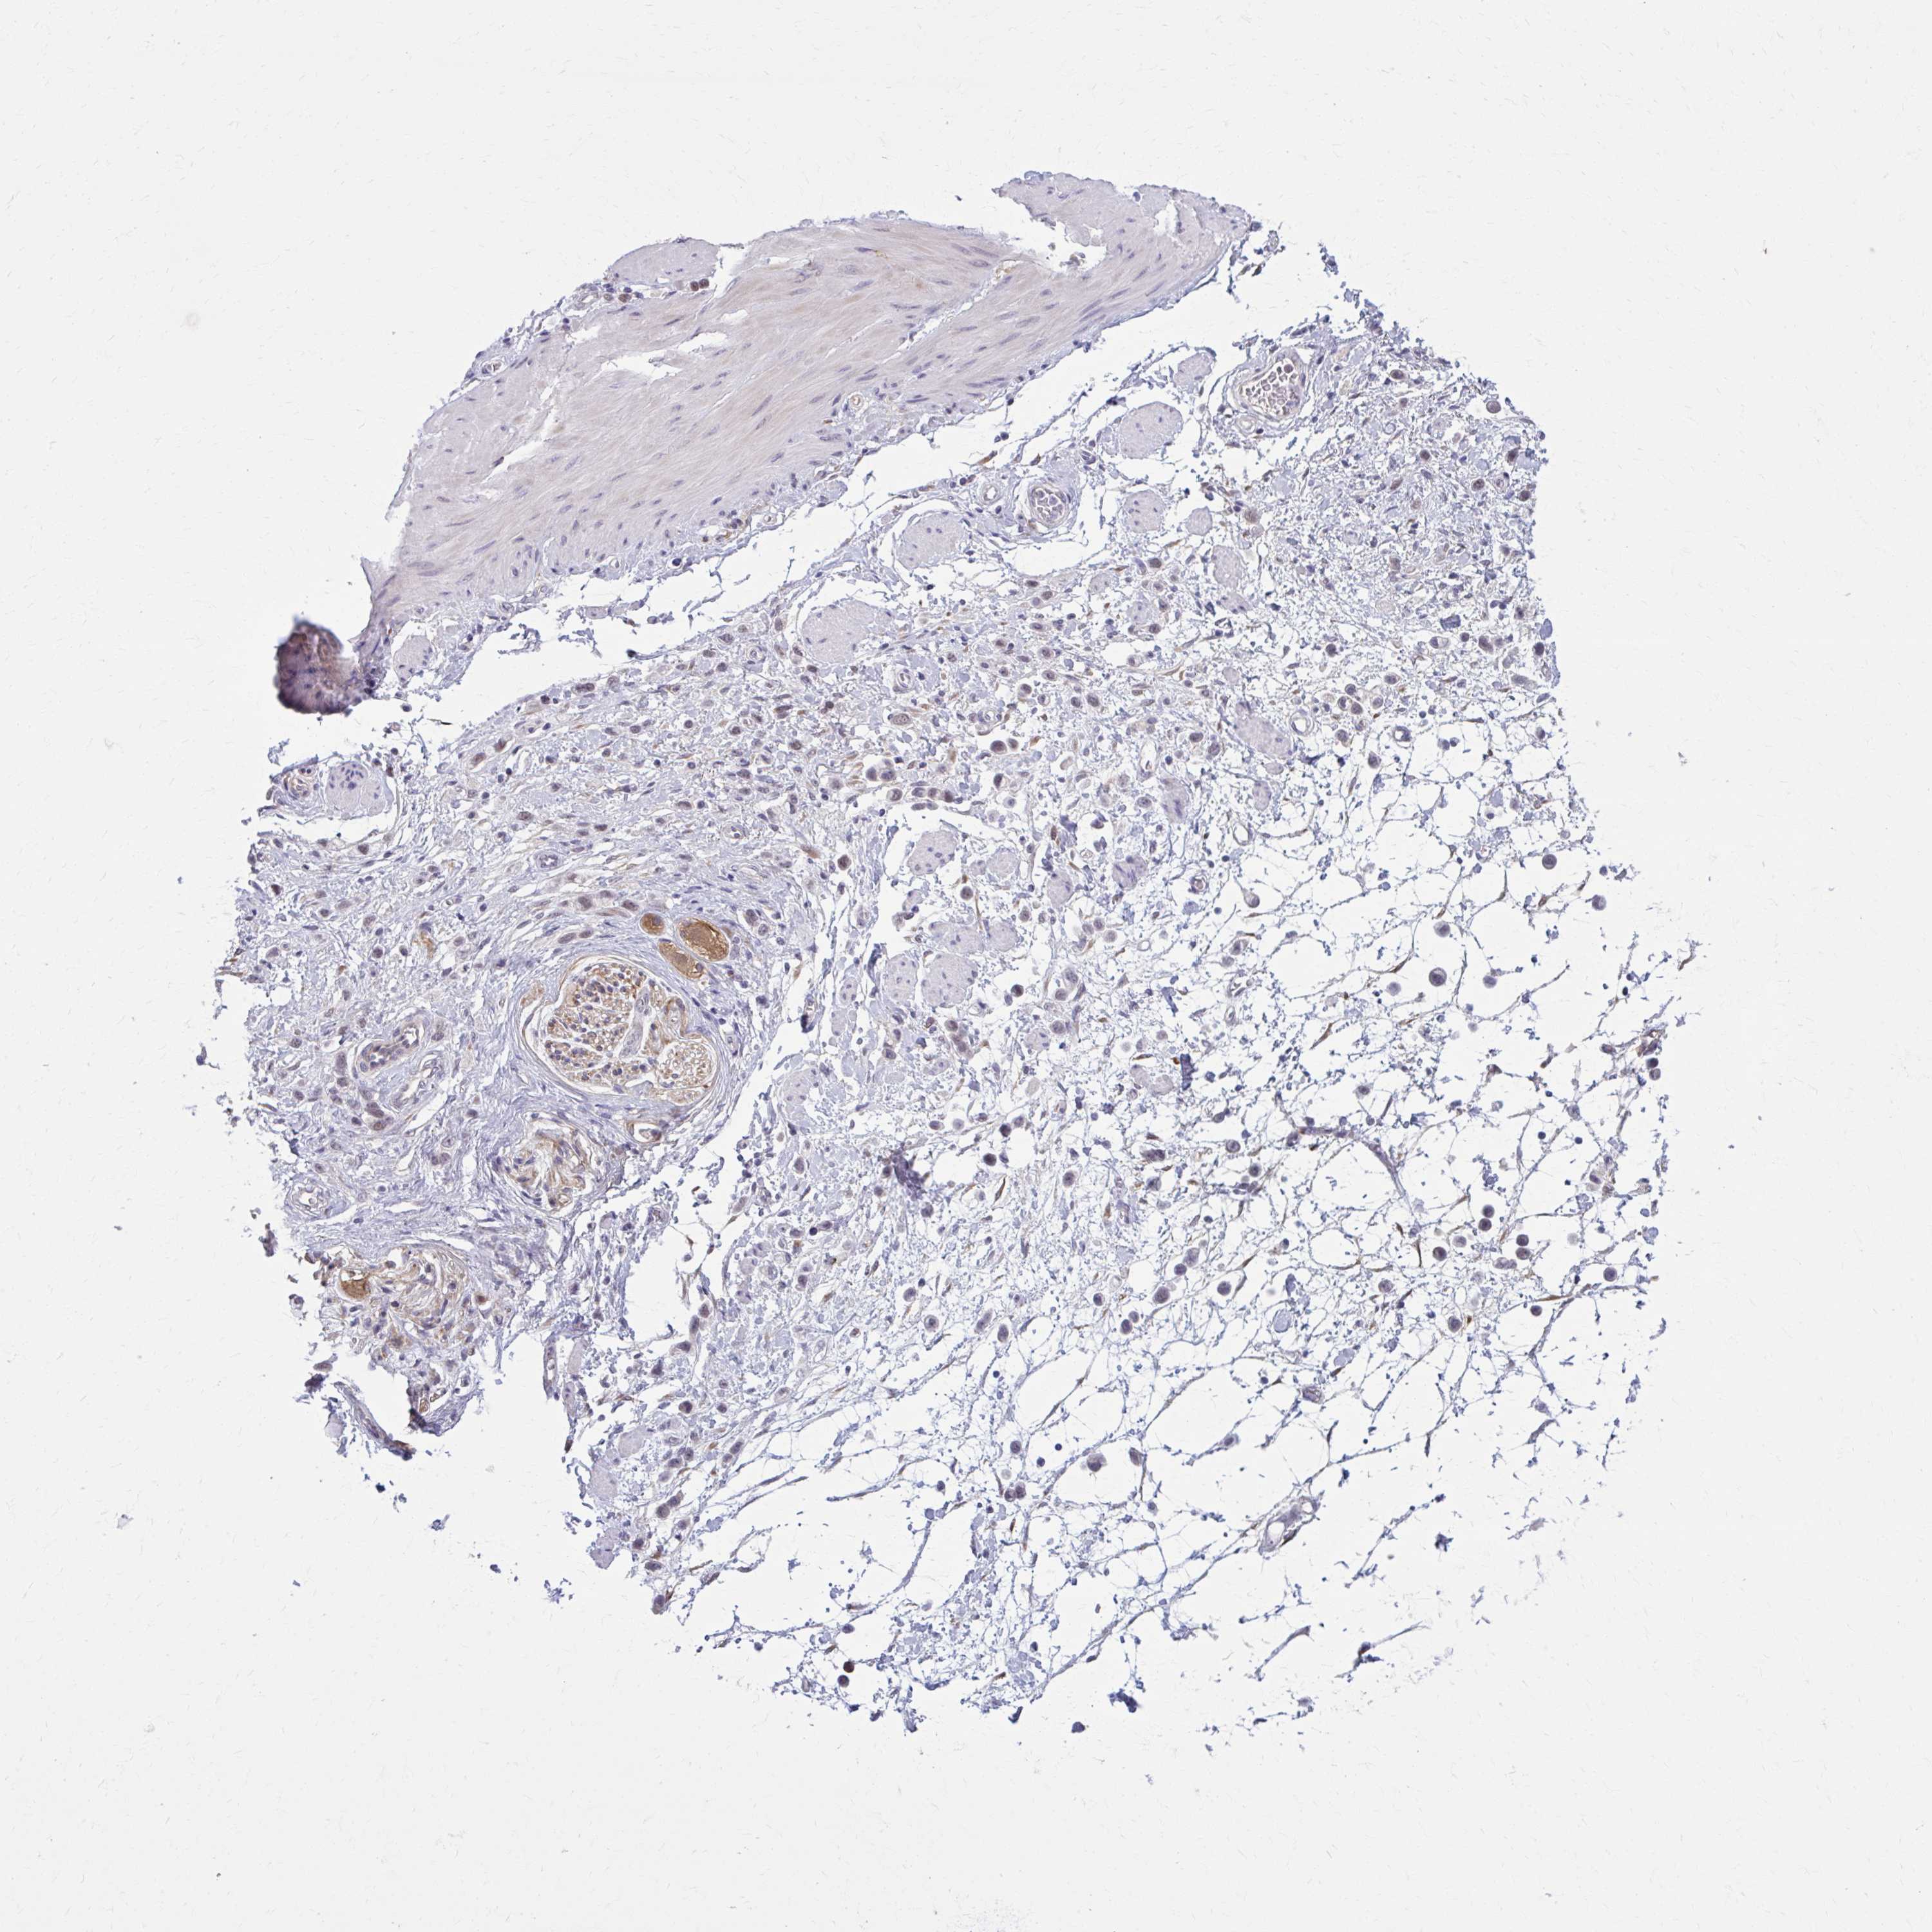

STOMACH CANCER - Protein expressioni

A mouse-over function shows sample information and annotation data. Click on an image to view it in a full screen mode. Samples can be filtered based on level of antibody staining by selecting one or several of the following categories: high, medium, low and not detected. The assay and annotation is described here.

Note that samples used for immunohistochemistry by the Human Protein Atlas do not correspond to samples in the TCGA dataset.

Antibody stainingi

Antibody staining in the annotated cell types in the current human tissue is reported as not detected, low, medium, or high, based on conventional immunohistochemistry profiling in selected tissues. This score is based on the combination of the staining intensity and fraction of stained cells.

Each image is clickable and will lead to virtual microscopy that enables deeper exploration of all samples and also displays staining intensity scores, fraction scores and subcellular localization as well as patient and tissue information for each sample.

Antibody HPA058251

Antibody HPA058380

Staining

High

Medium

Low

Not detected

Intensity

Strong

Moderate

Weak

Negative

Quantity

>75%

75%-25%

<25%

None

Location

Nuclear

Cytoplasmic/membranous

Cytoplasmic/membranous,nuclear

Adenocarcinoma, NOS